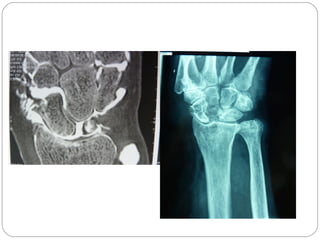

CT SCAN

CT permits accurate anatomic assessment of the fracture.

Bone contusions are not evaluated with CT, but true fractures can

be excluded

Most sensitive and specific

Multiplanar and 3D-reconstructions are possible.

IMAGING

XRAYS: 4 essential views

PA view

Lateral view identify majority

Supinated oblique of fractures

Pronated oblique

SCAPHOID VIEW: is a PA radiograph with the wrist

extended 30° and deviated ulnarly 20°. This view helps to

stretch out the scaphoid and is also used for assessing the

degree of scaphoid fracture angulation

A clenched-fist radiograph has also been useful for

visualization of the scaphoid waist.